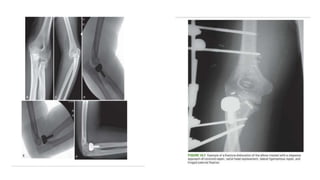

• Open reductionand repair of the soft tissues • Lateral collateral ligament is reattached using suture anchors or bone tunnels • If instability is present after LCL repair then MCL repair must be addressed. • If persistent instability is present: HINGED EXTERNAL FIXATION is done.

• 32.

TREATMENT OF TERRIBLETRIAD PRINCIPLES OF TREATMENT: 1. Restore coronoid stability through fracture fixation of type 2 and type 3 fractures, through anterior capsular repair of type 1 fracture 2. Restore radial head stability through fracture fixation or replacement with a metal prosthesis. 3. Restore lateral stability through repair of the lateral collateral ligament complex and associated secondary constrains such as common extensor origin and or posterolateral capsule.

4. Repair themedial collateral ligament in patients with posterior instability 5. Apply a hinged external fixator when the conventional repair does not establish sufficient joint stability to allow early motion.

FIXATION STRATEGY • Fromdeep to superficial 1. Fixation of coronoid 2. Anterior capsule repair 3. Radial head fixation or replacement 4. Lateral collateral ligament repair 5. Common extensor origin reattachment.